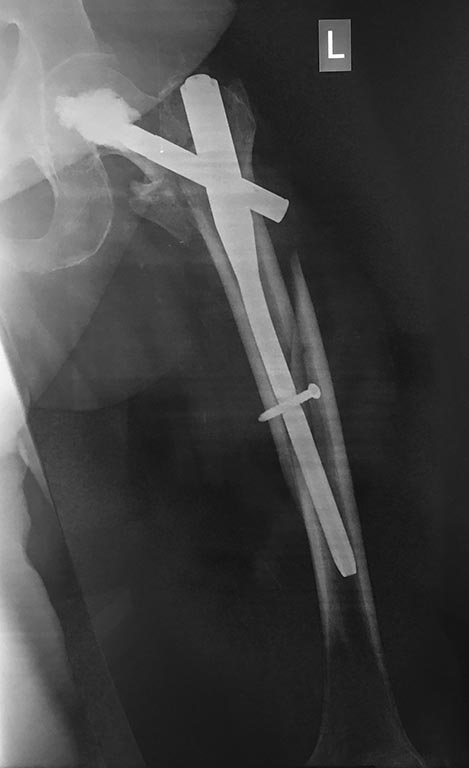

Шесть недель назад соматически отягощенная полная пациентка 91 года

прооперирована по поводу чрезвертельного нестабильного перелома бедра

Был выполнен остеосинтез цефаломедуллярным гвоздем с аугментацией

клинка. Не без труда, но пациентка восстановила прежний уровень

активности. Ходила без дополнительной опоры по квартире. Упала ночью,

получила перимплантный перелом. Понятно, что будем оперировать, и

быстро. Вопрос - чем и как? Не скрою, у меня есть предоперационный план,

но, совершенно не уверен, что мое решение единственно возможное в данной

ситуации. И, единственно правильное. Есть идеи?